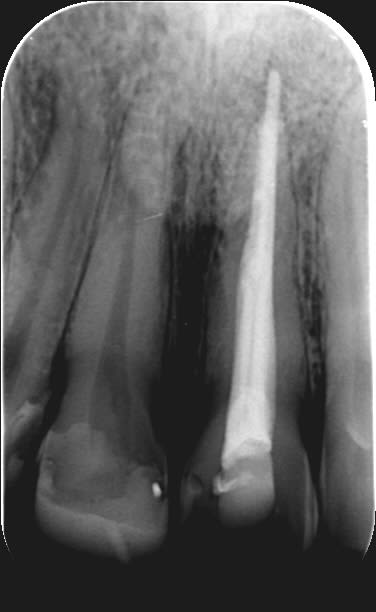

Endos sur 13-12 faites il y a 1 mois suite a un abcès avec fistule, mobilité ++++ des 2 dents, grosse image apicale, endos qui se sont droulés sans problème en condensation latérale, pas de radio contrôle faites ce jour là

j'ai revu aujourd'hui, mobilité nulle, gencive tiptop, plus de problèmes, je refais une radio contrôle et vois ça....

Bonne question, je pense que c'est un cône de gutta dans un canal latéral et dans la fistule....

J'ai pas fait de radio post-op, car il n'y avait rien d'anormal lors de l'obturation et c'est pas obligatoire chez nous. Je pense que c'est un cône de gutta accesoire ou du ciment qui a fusé à travers un canal latéral.

Je pense pour ma part, que c'est de la gutta qui a fusé puis remonté dans la lésion.

Mais pour en être certain, une seule chose à faire : Prendre 2 radio de cette dent; la première perpendiculaire au capteur, et la seconde décalée (mésialement ou distalement sans bouger le capteur : règle de Clarck)

J’aurais aimé pouvoir compter sur quelques tests pulpaires au préalable ( sur la canine et sur la latérale), mais, à vue d’œil , en admettant que les deux dents ne répondaient ni au test thermique ni au vitalomètre, il y a possibilité que ce soit peut être une nécrose au niveau de la latérale, de la canine (j’en doute) et un kyste fissuraire latéral concomitant. Ne le penses tu pas? Le site pour un tel kyste est le bon et les deux dents semblent refoulées par la lésion. Peut-être n’as tu réglé que la moitié du problème en ne faisant que l’endo ?